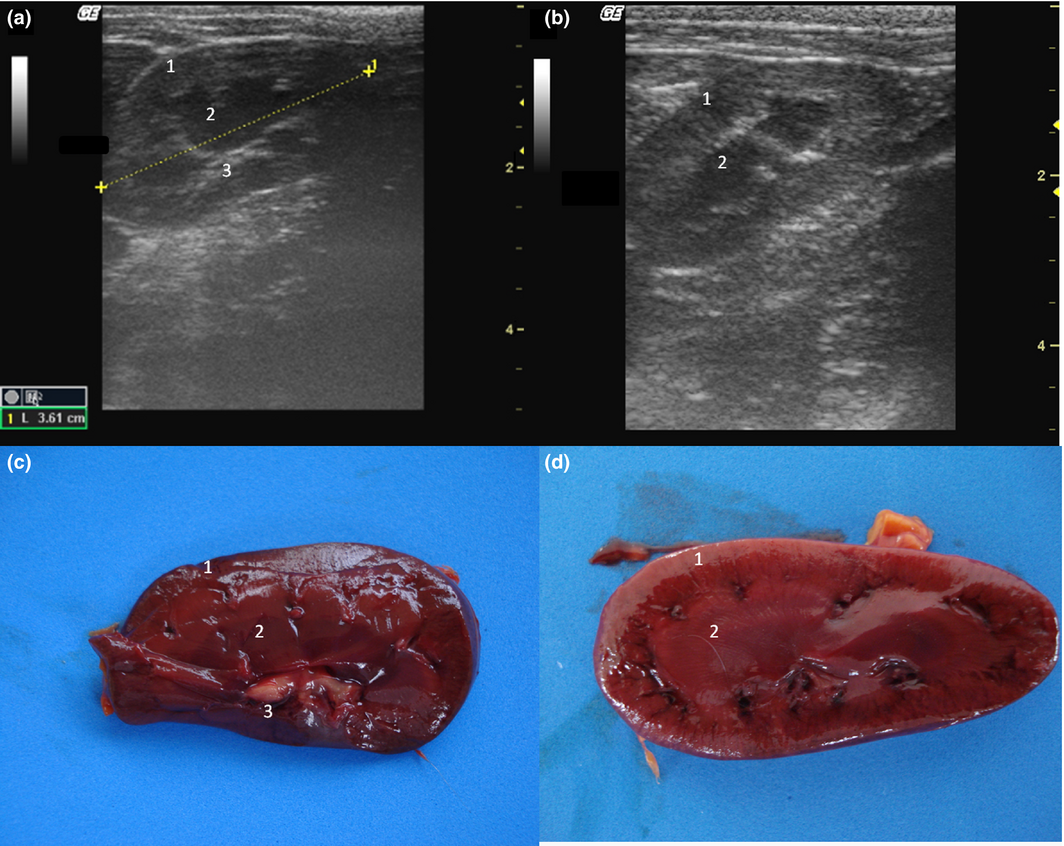

The kidneys were observed in the retroperitoneal space. The left kidney was evaluated caudal to the gastric fundus and the right was identified in the renal fossa of the right liver in all individuals. Kidneys lengths (average of 3.81 cm), are described in Table 1. The renal outlines were well defined and regular, delineated by a thin hyperechogenic line, the renal capsule (Fig. 2a,b). It was possible to identify and delineate the cortical, medullary and renal pelvis regions in all individuals. The cortex showed homogeneous echotexture and it was isoechoic to hyperechoic to the liver parenchyma and isoechoic when compared with the splenic parenchyma. The medullary region was well defined and appeared hypoechogenic in relation to the cortex. The pelvis was hyperechoic in relation to other parts of the kidney, possibly due to the fat present in this region. Discrete pyelectasis (0,2–3 mm) was observed in at least one kidney in five monkeys. This finding is assumed to be due to the fluid therapy or a normal variant. The relationship among cortical and medullary regions was measured, averaging proportion of 1:1. Post-mortem study of the kidneys allowed a better understanding of the anatomy (Fig. 2c,d). Medullary rim sign was not observed in any individual.

Figure 2.

(a,b) Sonogram of the kidney in frontal (a) and sagittal (b) image planes. (c,d) Post-mortem comparative study of the kidney on a frontal view (c) and sagittal view (d). 1 – Cortical, 2 – Medullar, 3 – Renal pelvis.

The gallbladder had homogeneous anechoic fluid content; luminal debris was not detected. The gallbladder wall was totally or partially visualized as a hyperechoic line when compared with the hepatic parenchyma, average measuring 1.5 mm thick. Post-mortem studies allowed identification of liver lobes: papillary process of the caudate lobe, caudate process of the caudate lobe, left lobe, quadrate lobe and right lobe; this allowed for a comparison of ultrasound imaging and anatomic position (Fig. 5).

Figure 5.

Post-mortem preparation of Alouatta fusca liver (anterior view), showing the disposition of the gallbladder (GB) and hepatic lobes: (1a) papillary process of the caudate lobe, (1b) caudate process of the caudate lobe, (2) left lobe, (3) quadrate lobe, (4) right lobe.